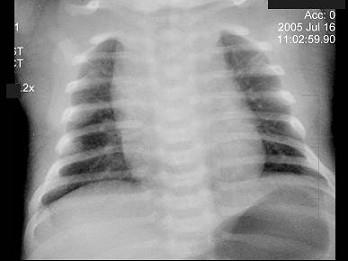

问题 患儿,男,1天,生后呼吸困难,有窒息史,如图,最可能的诊断为?(?)

选项 A.新生儿肺炎 B.新生儿湿肺 C.新生儿肺出血 D.新生儿呼吸窘迫综合症 E.胎粪吸入综合征

答案 A